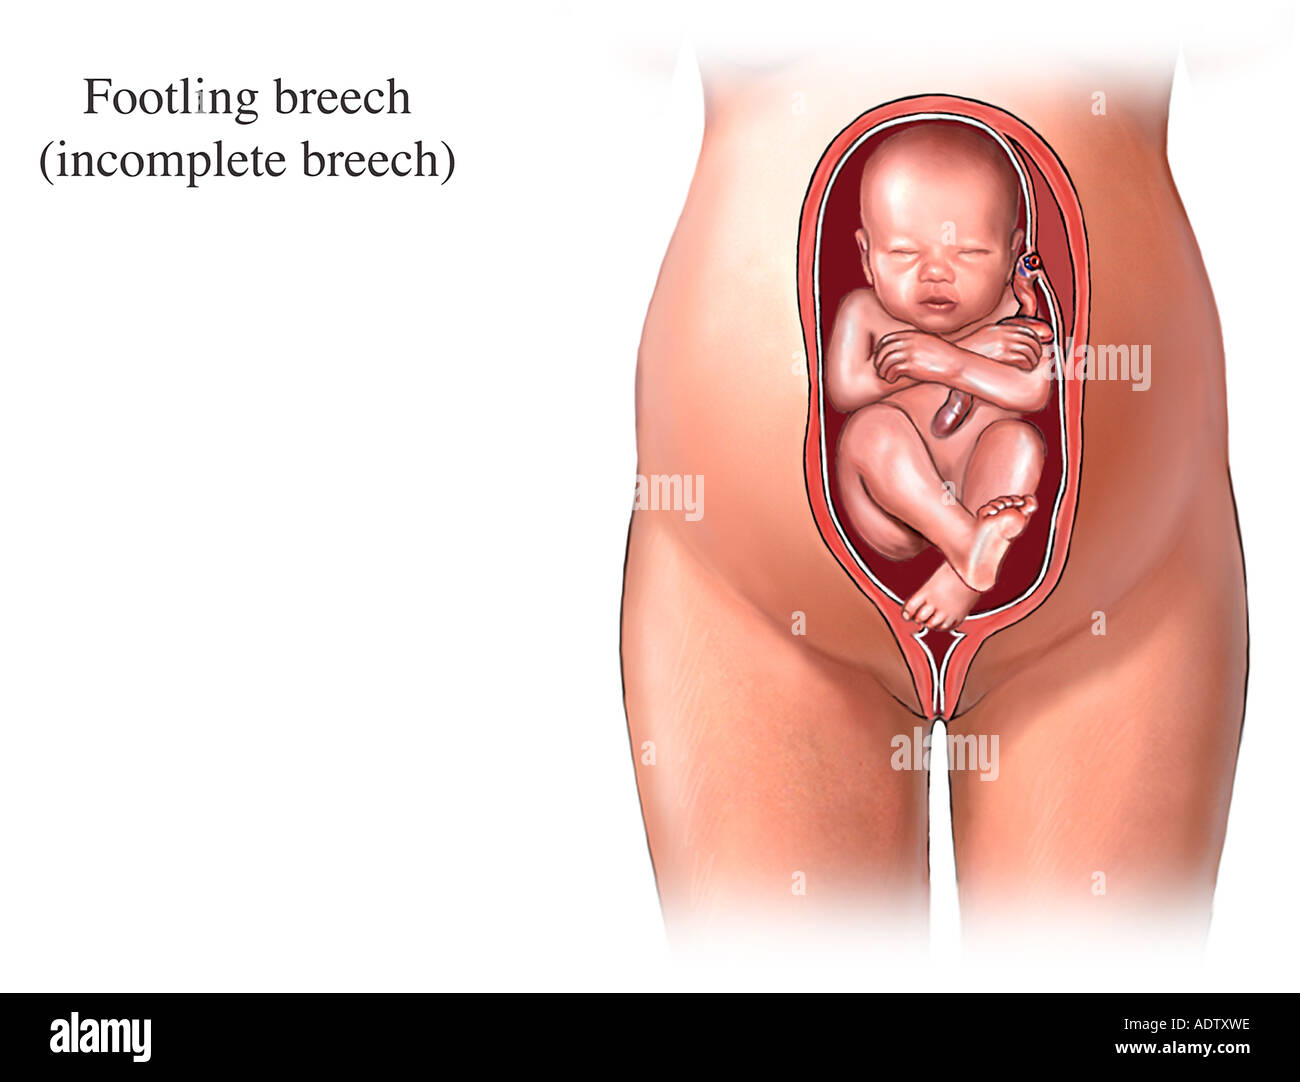

Breech.webp)

Расположение ребенка и пуповины

Живот с ягодичным предлежанием

External Cephalic Version(ECV) technique for Breech Baby

Метод Цовьянова при ягодичном предлежании

Пособие по Морисо Левре Лашапель

Рождение ребенка в тазовом предлежании

Первый момент биомеханизма родов при тазовом предлежании